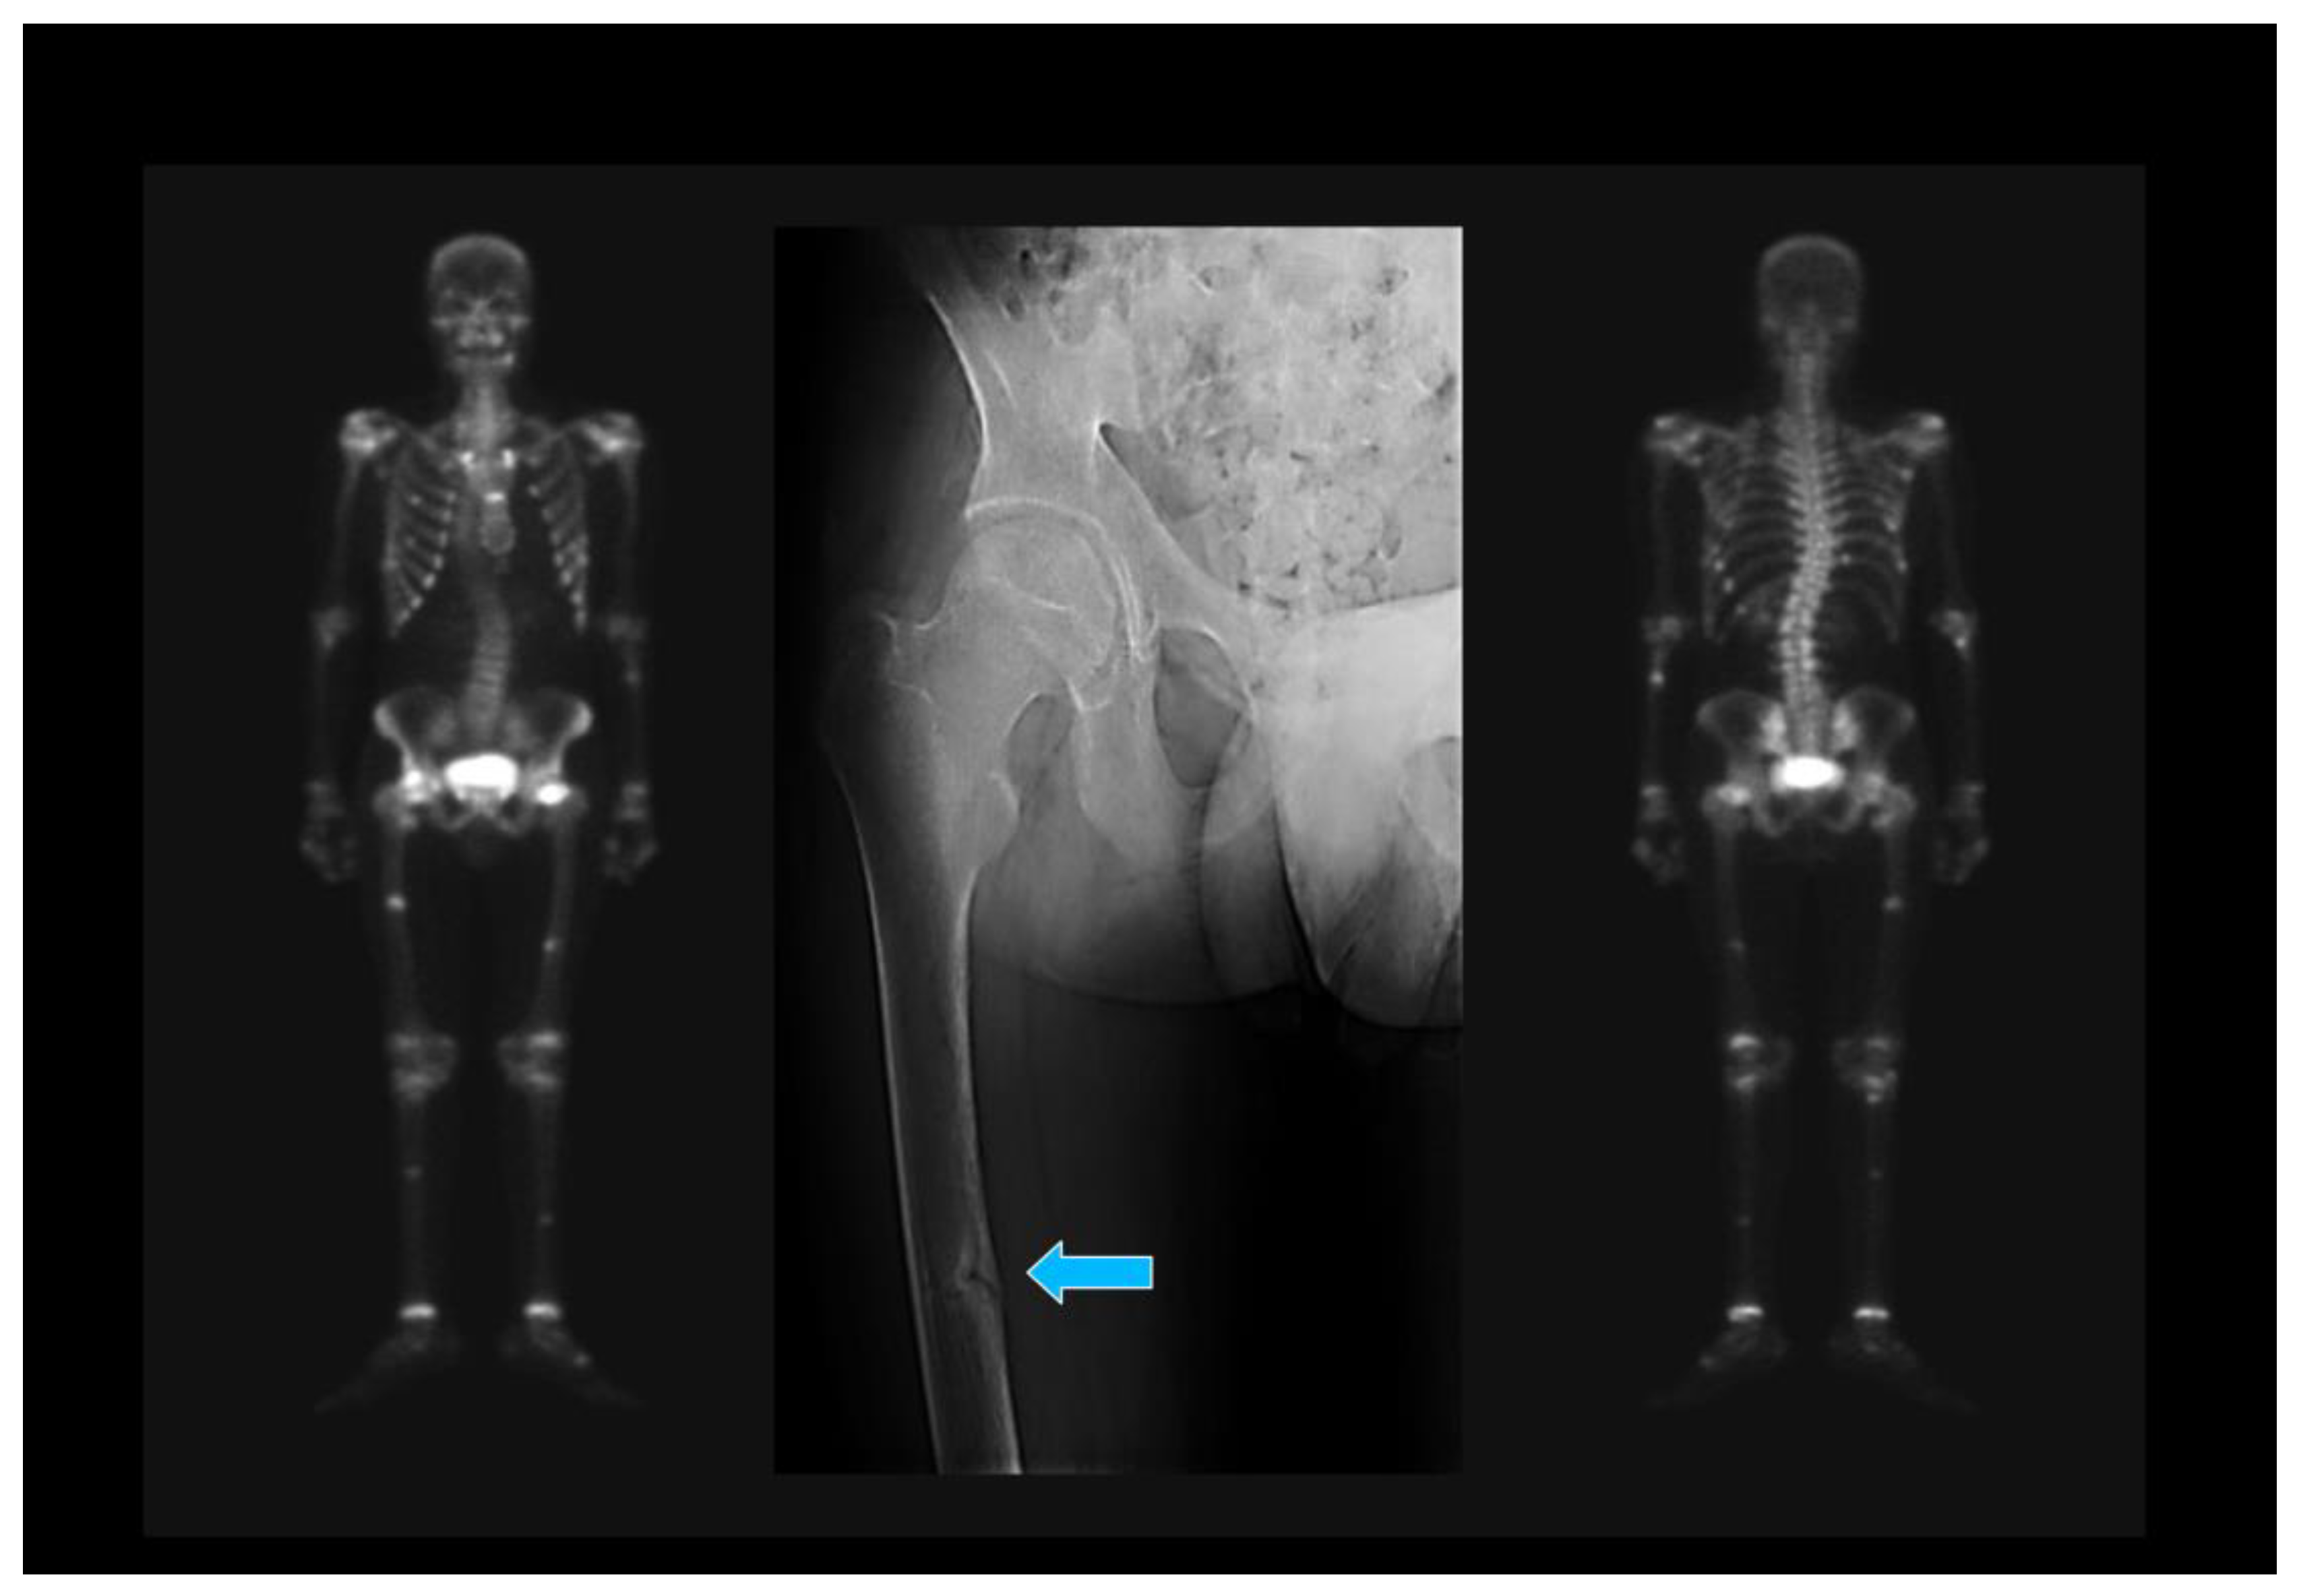

5.3. Oncogenic Osteomalacia

- Gupta, A.; Kandasamy, D.; Sharma, R.; Damle, N.; Goyal, A.; Goyal, A.; Agarwal, S.; Dharmashaktu, Y. Imaging characteristics of phosphaturic mesenchymal tumors. Acta Radiol. 2023, 2841851231160086. [Google Scholar] [CrossRef]

- Minisola, S.; Peacock, M.; Fukumoto, S.; Cipriani, C.; Pepe, J.; Tella, S.H.; Collins, M.T. Tumour-induced osteomalacia. Nat. Rev. Dis. Prim. 2017, 3, 17044. [Google Scholar] [CrossRef]